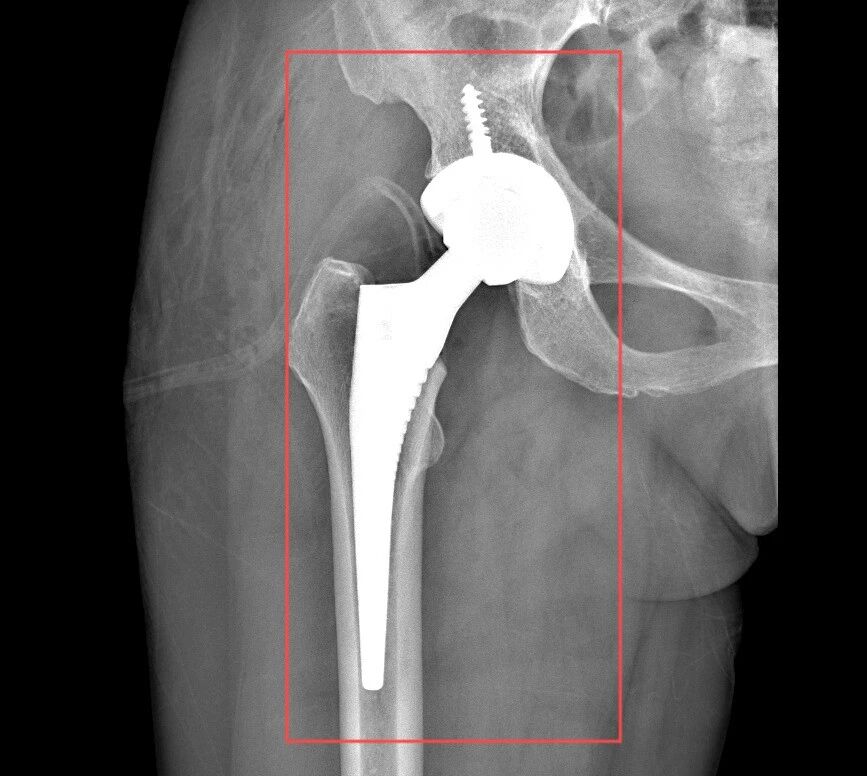

患者术前、术后CT

随后,张锡光带领MDT联合会诊团队再次针对患者病情及诊疗方案进行认真研究,反复分析讨论,确定由张锡光主刀,创伤中心副主任蔡志荣协助,为患者实施全髋关节置换手术;其他相关科室则为患者可能出现的突发情况做好相应准备。

无影灯下,张锡光以精确至毫厘的动作实施着手术操作。医疗团队在默契协作中形成精密的工作闭环,每个环节都如齿轮啮合般严丝合缝。基于患者特殊的身体状况,张锡光精准把握手术节奏,凭借行云流水般的手术技法,仅用半小时便完成创口仅8cm大小的微创手术,全程零输血的操作既保障了患者机体代偿能力,更赢得关键性康复窗口期。术后次日清晨,杨女士已能借助助行器完成自主移行训练。康复医学科团队更创新性构建起三管齐下的复健方案,涵盖运动功能重塑、营养代谢优化及心理韧性建设等多维度的精准干预,用医学专业与温暖人文编织起全周期的康复守护网。